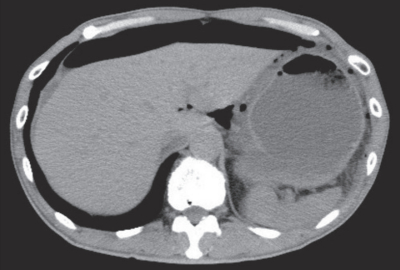

血液所見:赤血球 488万、Hb 14.8g/dL、Ht 44%、白血球12,200、血小板33万。血液生化学所見:総蛋白 6.1 g/dL、アルブミン 3.1 g/dL、総ビリルビン 0.2 mg/dL、AST 18 U/L、ALT 19 U/L、LD 135 U/L(基準120~245)、尿素窒素 10 mg/dL、クレアチニン 0.7 mg/dL。CRP 1.7 mg/dL。腹部単純CTの軟部条件と肺野条件を別に示す。